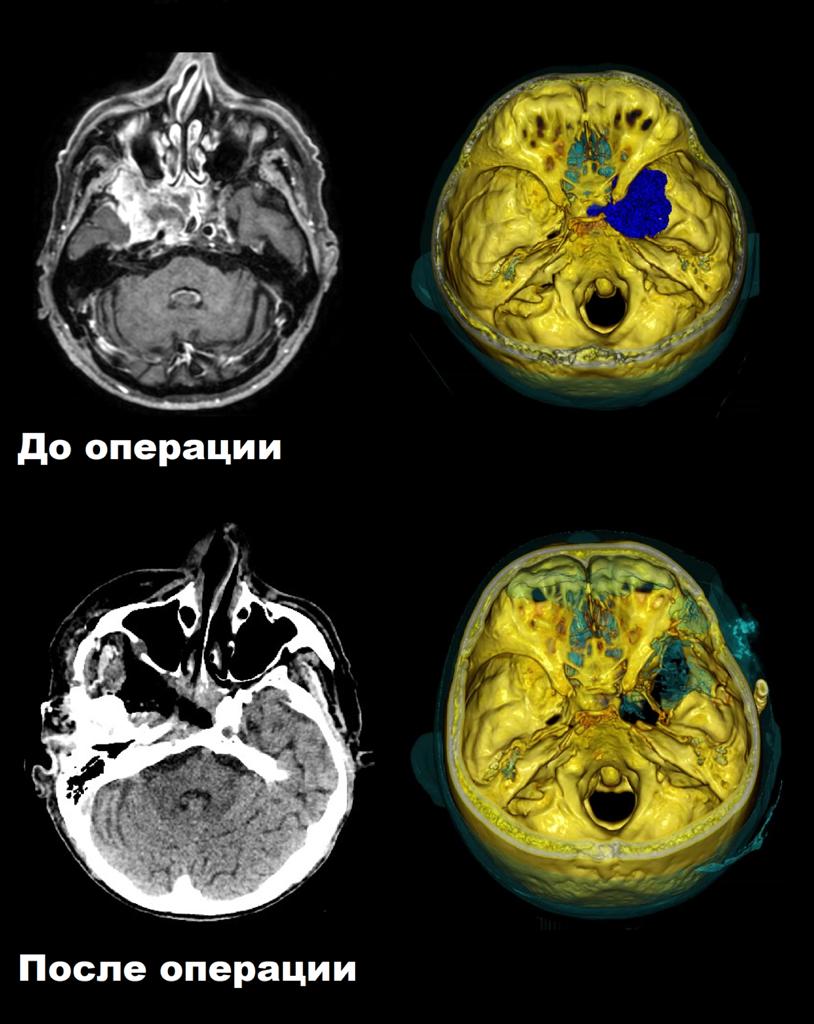

В нейрохирургическом отделении ФЦМН ФМБА России провели сложную операцию у пациента с большой распространенной опухолью, прорастающей ткани лица и проникающей в головной мозг.

Мужчина 70-ти лет поступил на лечение в ФЦМН по федеральной квоте на высокотехнологическую медицинскую помощь. В 2016 г. пациент был оперирован по поводу рака языка (выполнена гемирезекция языка справа, гистологически — плоскоклеточная карцинома), после чего он прошёл курс химиолучевой терапии. В 2018 г. стала беспокоить язва в области мягкого неба. При биопсии выявлена плоскоклеточная карцинома G1. Пациент прошёл лучевую терапию на область опухоли мягкого неба и последующую химиотерапию. С весны 2020 г. у пациента появились лицевые боли по типу невралгии тройничного нерва справа, глазодвигательные нарушения. При МРТ головного мозга выявлена краниофациальная опухоль справа.

Пациенту провели операцию по удалению опухоли, а также уточнения гистологического типа последней. Сама операция не являлась рутинной для хирурга ввиду обширного распространения опухоли с захватом и прорастанием множества тканей и жизненноважных структур. Залог успеха при таких операциях: тщательное планирование хирургического доступа на основании данных КТ и МРТ, применение средств интраоперационной навигации, применение микроскопии, а также тончайшее и деликатное владение микрохирургическими инструментами в процессе удаления.